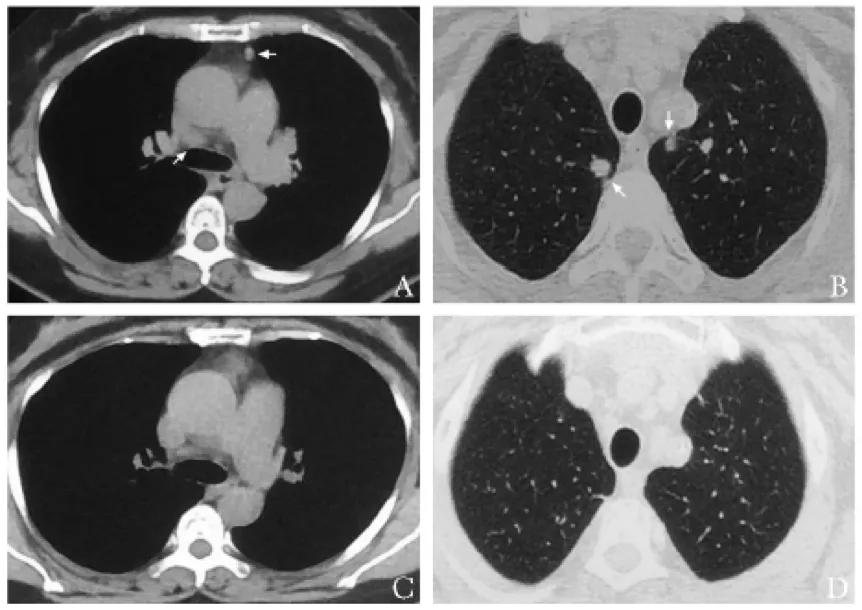

【图1】与两年前胸部CT(图A、图B)对比,本次就诊胸部CT(图C、图D),对比可见原箭头所示肺内结节明显缩小,纵隔淋巴结较前缩小。

小总结:56岁女性肺内结节伴淋巴结肿大2年余,吸入糖皮质激素后好转,近期病情反复。胸部CT见图1,心电图可见室早、房早、房速及ST-T改变,超声心动图提示全心增大,二三尖瓣少量反流及少量心包积液……